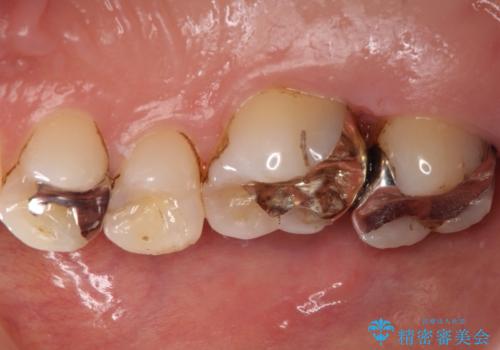

- 他院で装着された保険の前歯のかぶせ物が、他と歯と馴染まないので、自然な歯にしたいとのことで来院されました。

右上の1番目の歯の保険のかぶせ物と金属の土台を、ファイバーコアとオールセラミックにて再補綴する計画としました。

形態も色調もまわりの歯とは、調和がとれておらず、目立っていました。

今回治療することで、自然な前歯になったと喜んでいただけました。